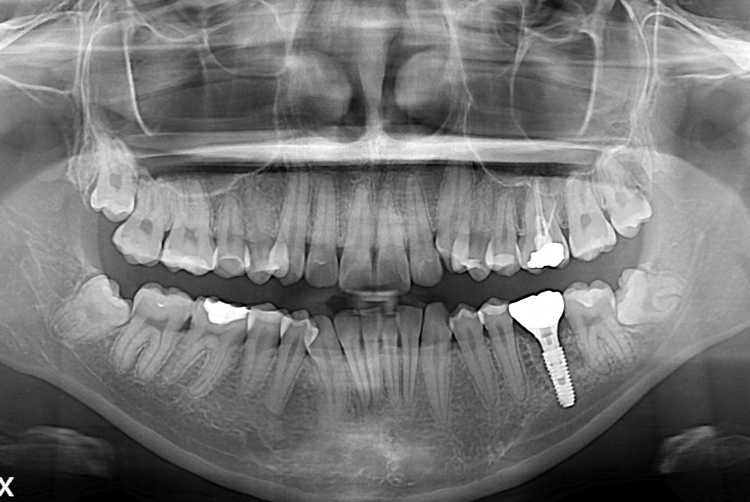

[임플란트] 어금니 임플란트

치료후 : 2017-05-18

세종치과는 많은 환자와 다양한 케이스를 바탕으로

항상 편안한 임플란트 수술을 제공하고자 노력하고,

오래동안 튼튼히 쓸 수 있는 임플란트 수술을 가장 큰 목표로 삼고 있습니다.